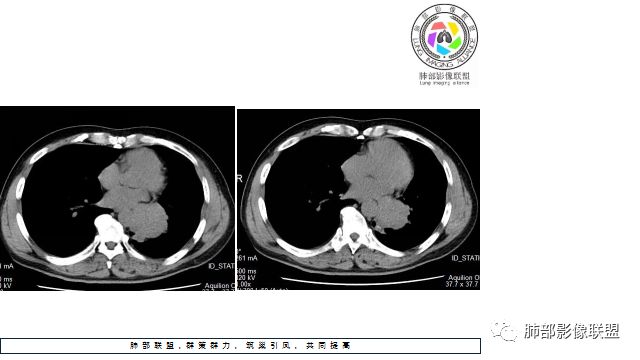

1.左下肺门区巨大肿块,支气管显示不清,轻度阻塞性炎症,没有明显肺不张,提示管腔受压狭窄可能性大于堵塞,这较少见于鳞癌。

2.病灶边缘光滑,未见明显分叶、毛刺,未见明显强化,这符合腺癌影像学特点,却符合神经内分泌癌表现。

3.病灶内密度均匀,轻到中度均匀强化,大病灶未见明显液化坏死区及空洞,不符合鳞癌而符合小细胞肺癌特点。

4.病灶内有肺动脉走形,血管局部受压,未见破坏,病灶乏血供,呈血管包埋或血管造影征;侵袭性力强及破坏力弱、血管漂浮都符合SCLC,所以鳞癌的可能性也不大。

5.左肺门块影或淋巴结肿大,竭力挤兑肺门血管结构,呈冰冻肺门;有时候SCLC可以单独呈现冰冻肺门,而没有没有冰冻纵隔。

7.须特别注意的是,肺门区的融合块影,不排除它可能仅仅为转移淋巴结。